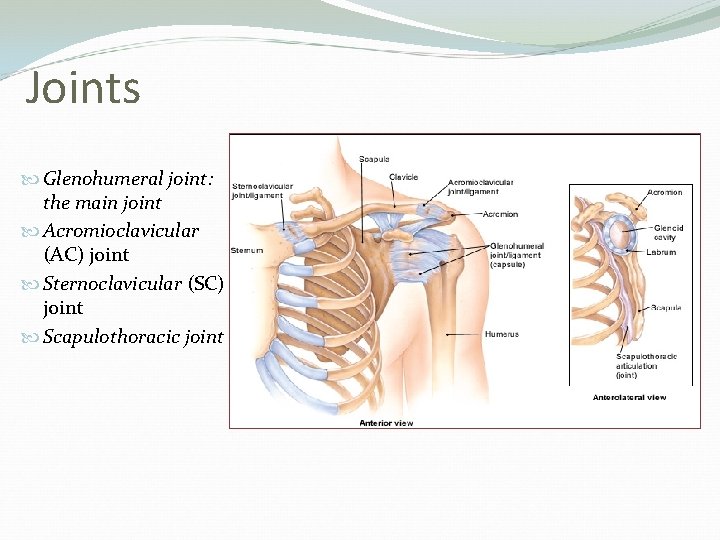

Joints Glenohumeral joint: the main joint Acromioclavicular (AC) joint Sternoclavicular (SC) joint Scapulothoracic joint